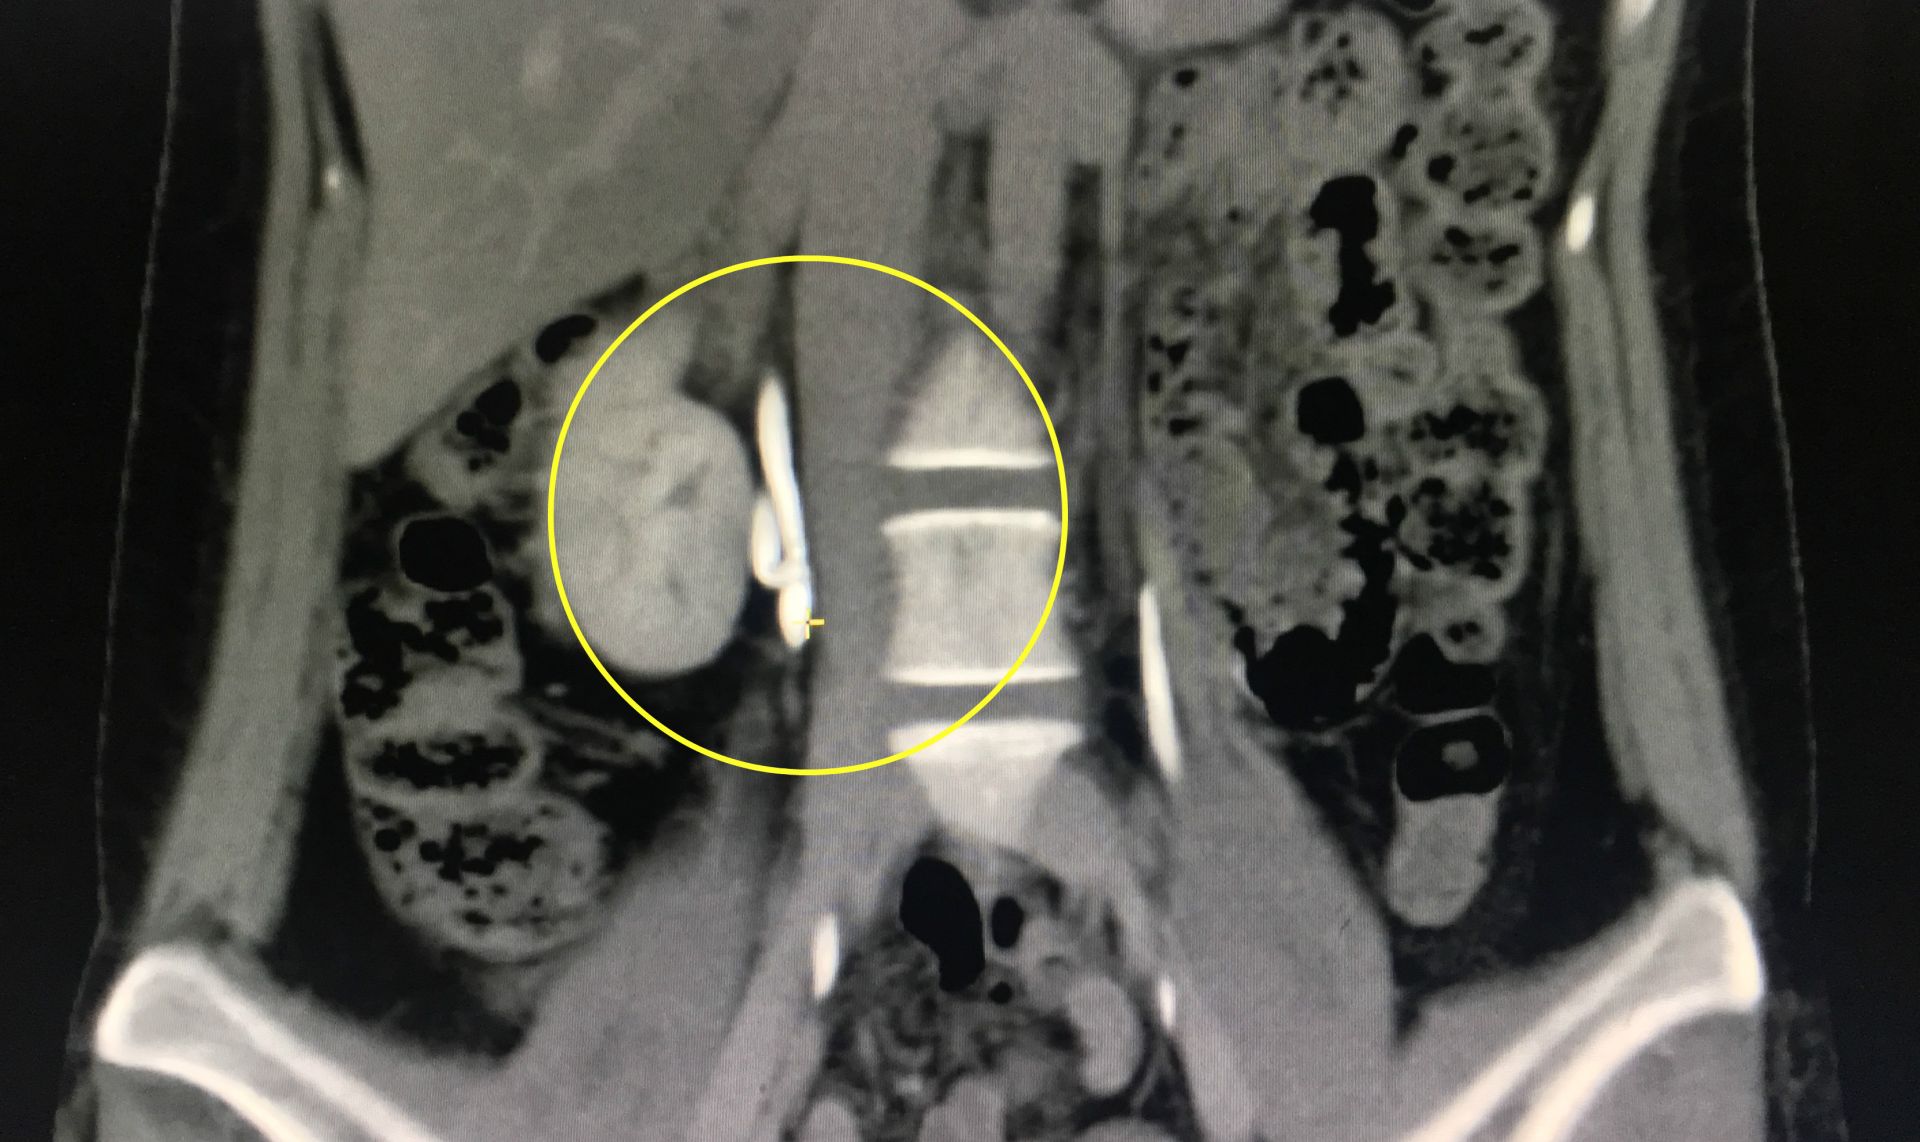

▲黃圈處是患者右側的兩條輸尿管。(圖/南投醫院提供)